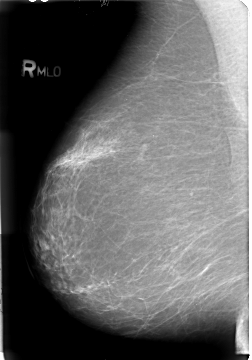

B_3018_1.RIGHT_MLO

RIGHT_CC LINES 4568 PIXELS_PER_LINE 3072 BITS_PER_PIXEL 12 RESOLUTION 50 NON_OVERLAY

RIGHT_MLO LINES 4680 PIXELS_PER_LINE 3264 BITS_PER_PIXEL 12 RESOLUTION 50 NON_OVERLAY